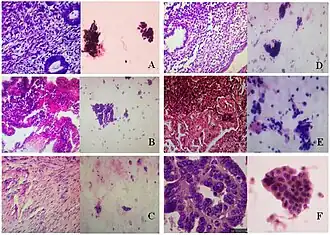

(A) proliferative endometrium (Left: HE × 400) and proliferative endometrial cells (Right: HE × 100)

(B) secretory endometrium (Left: HE × 10) and secretory endometrial cells (Right: HE × 10)

(C) atrophic endometrium (Left: HE × 10) and atrophic endometrial cells (Right: HE × 10)

(D) mixed endometrium (Left: HE × 10) and mixed endometrial cells (Right: HE × 10)

(E): endometrial atypical hyperplasia (Left: HE × 10) and endometrial atypical cells (Right: HE × 200)

(F) endometrial carcinoma (Left: HE × 400) and endometrial cancer cells (Right: HE × 400).